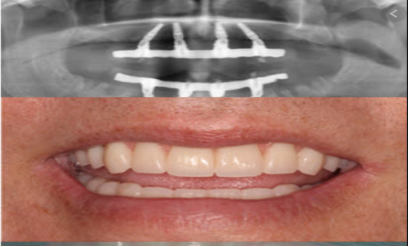

六、All on 4全口重建成果展示

Step1:拍X-Ray和CT,術前評估身體狀況與治療

由於全口重建涵蓋許多不同的齒科項目,除了先為病患照全口X光,還需對全方位瞭解,比如瞭解病患慢性疾病、服抗凝血藥物、進行過放射線治療等,患者是否有冠心病、糖尿病、高血壓等。